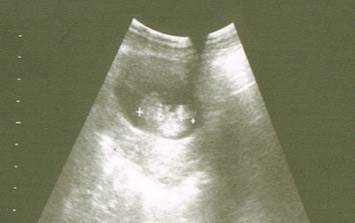

La ecografía de la semana 8 ya puede realizarse por vía abdominal, aunque depende mucho del aparato del que se disponga. Siempre es importante llevar la vejiga llena de orina para facilitar la visión del útero con la vesícula gestacional en su interior en estas primeras semanas de embarazo.

También debes saber que algunas pacientes transmiten mal los ultrasonidos o son obesas y eso dificulta la visualización a través de la pared abdominal. En estos casos, se debe realizar una ecografía vaginal. En la ecografía, se visualizan pequeños movimientos verticales del embrión, así como el latido cardiaco.

Imágenes del latido cardiaco y vesícula del embrión

Muchos obstetras realizan la primera ecografía en la semana 8 para asegurar la visualización del embrión así como su viabilidad, confirmada por el movimiento embrionario y el latido cardiaco. Si se hace una ecografía antes de la semana 8, muchas veces podemos no ver latido cardiaco, pero eso no significa que se haya interrumpido la gestación, sino que aún es muy incipiente y la gestante está de menos tiempo del calculado.